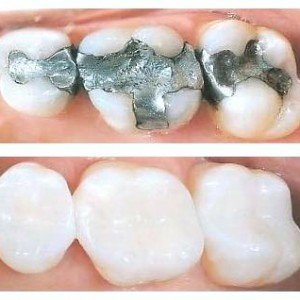

الحشوات التجميلية

جدول المحتويات ابتسامتك هي عنوان ثقتك، لكن هل يُخفي تسوس الأسنان جمالها؟ لا تدع هذه المشكلة تؤثر على مظهرك أو راحتك. فهل تعرف ما هي الحشوات التجميلية وكيف تختار الأفضل لك؟ ما هي الحشوات التجميلية؟ الحشوات التجميلية هي مواد تُستخدم لتحسين مظهر الأسنان المصابة أو المتضررة، ويعتمد اختيار نوع الحشوة على طبيعة ودرجة التلف […]